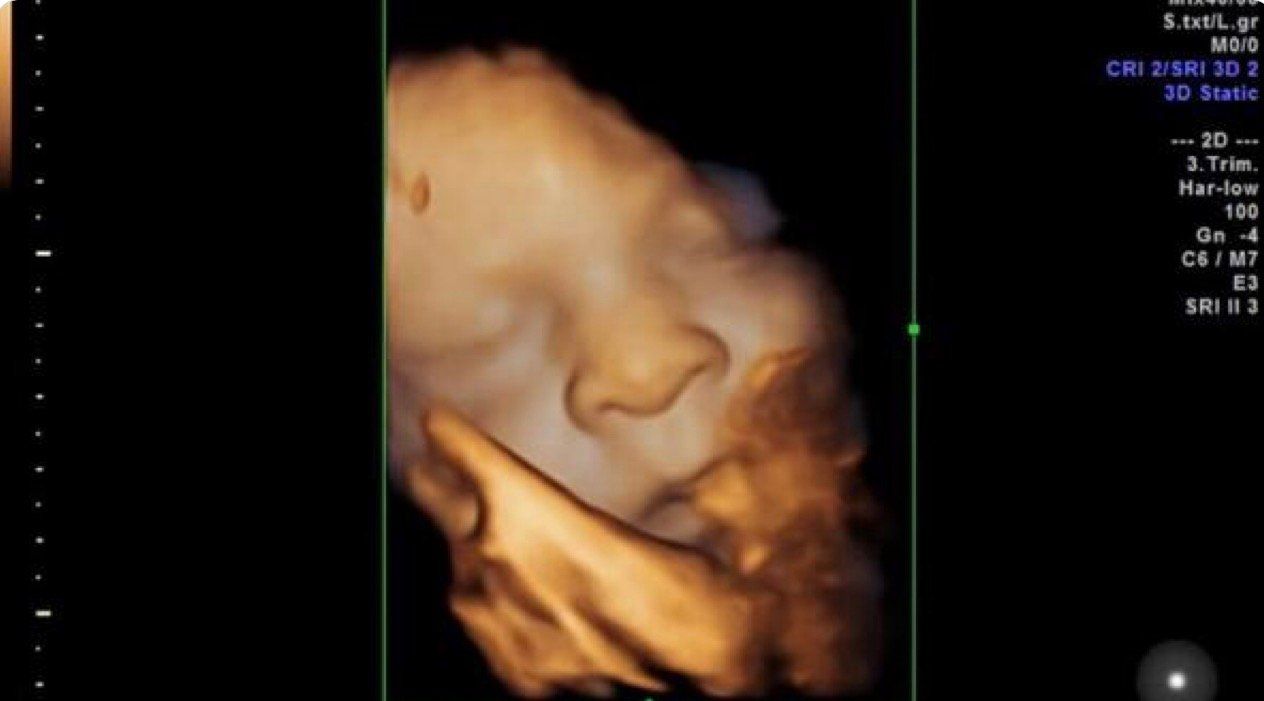

- Ecografía de tercera dimensión o 3D

El ecógrafo: Voluson® E8 es una plataforma de imágenes que usa tecnología de avanzada, es un sistema de ecografía líder en asistencia sanitaria para mujeres de una nueva generación donde es importante el diagnóstico temprano de malformaciones congénitas para determinar un tratamiento adecuado del feto en pro de su bienestar. La calidad de imagen gracias a sus herramientas vanguardistas nos hace a los perinatólogos los profesionales capaces de intervenir casos difíciles en su manejo. La tecnología HDlives del ecógrafo Voluson e8 expert permite ver el feto en el modo más cercano a una imagen directa sin necesidad de penetrar a la cavidad uterina como se hace en cirugía observando al feto en toda su superficie. El HDlive Ilumina los detalles finos del feto.

HDlive funciona con un mecanismo de combinación de tecnologías en volumen y una segunda generación dinámica de motor de renderizado para representar la del piel feto. El ultrasonido convencional utiliza una fuente de luz fija que refleja la luz de la superficie de la piel. HDlive proporciona una fuente de luz virtual móvil y calcula la propagación de la luz a través de la piel y el tejido. El perinatólogo puede colocar libremente la luz en cualquier ángulo en relación con el volumen de ultrasonido para iluminar áreas de interés. El posicionamiento de la fuente de luz detrás de un área específica del feto la cual no es vista en ese momento por el médico hace que esta aparezca para ser estudiada. HDlive ayuda a proporcionar una claridad extraordinaria en la imagen nunca antes vista y ayuda a realizar diagnósticos más tempranos debido a la capacidad de revelar detalles finos no posibles hasta este momento. HDlive ayuda a enriquecer la comunicación médico-paciente, así como facilitar una comprensión aun más completa de los resultados de los exámenes.